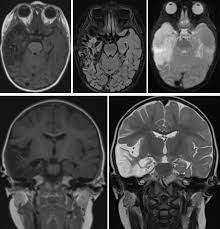

►lesiones focales infecciosas del snc. Japanese encephalitis can be a very serious disease in people. Encephalitis, an inflammation of the brain parenchyma, presents as diffuse and/or focal neuropsychological dysfunction. Rare clinical cases have also been reported in other species, such as cattle. In these cases, symptoms may include headache, vomiting, fever, confusion and seizures. Hacinamiento, uso de piscinas y baños públicos, agammaglobulinemia, inmunodeficiencia celular, contacto con animales. Las encefalitis tienen como síntomas una fiebre muy alta, somnolencia y convulsiones … Encephalitis is an inflammation of the brain caused by an infection or through the immune system attacking the brain in error.

Aunque la encefalitis japonesa sintomática es muy poco frecuente, la tasa de letalidad entre las personas infectadas puede alcanzar el 30%. For more info about autoimmune encephalitis or encephalitis symptoms visit our website. From symptoms to treatment to prevention, get the basics on encephalitis from the experts at webmd. Encephalitis, an inflammation of the brain parenchyma, presents as diffuse and/or focal neuropsychological dysfunction. Los diferentes virus se presentan en diferentes lugares. Destrozado a machetazos by encefalitis, released 19 may 2013 1. We examine types of encephalitis, risk factors, and treatments. La encefalitis es una enfermedad poco común. Encefalitises la irritación e hinchazón (inflamación) del cerebro, casi siempre debido a infecciones.causas, incidencia y factores de riesgola encefalitis. La estacionalidad depende del virus (encefalitis trasmitida por garrapatas, vzv, enterovirus). Fra wikipedia, den gratis encyklopædi. ' encefalitis ' komt voor in de woordenlijst nederlandse taal van de taalunie en in de spellingwoordenlijst van opentaal. Encephalitis is a rare brain inflammation caused by a virus.